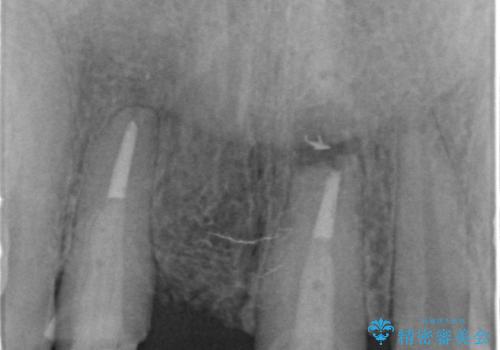

現在装着されているブリッジを除去したところ、歯ぐきよりも上に存在する歯質(縁上歯質)が少なく、土台の形態の悪さや不適合などさまざまな問題があります。

根管治療を行ったのち、歯周外科を行うことで、欠損部の歯ぐきの厚みを出し、縁上歯質を獲得することで、長期的な予後の見込めるブリッジを製作できる環境を整備していきます。